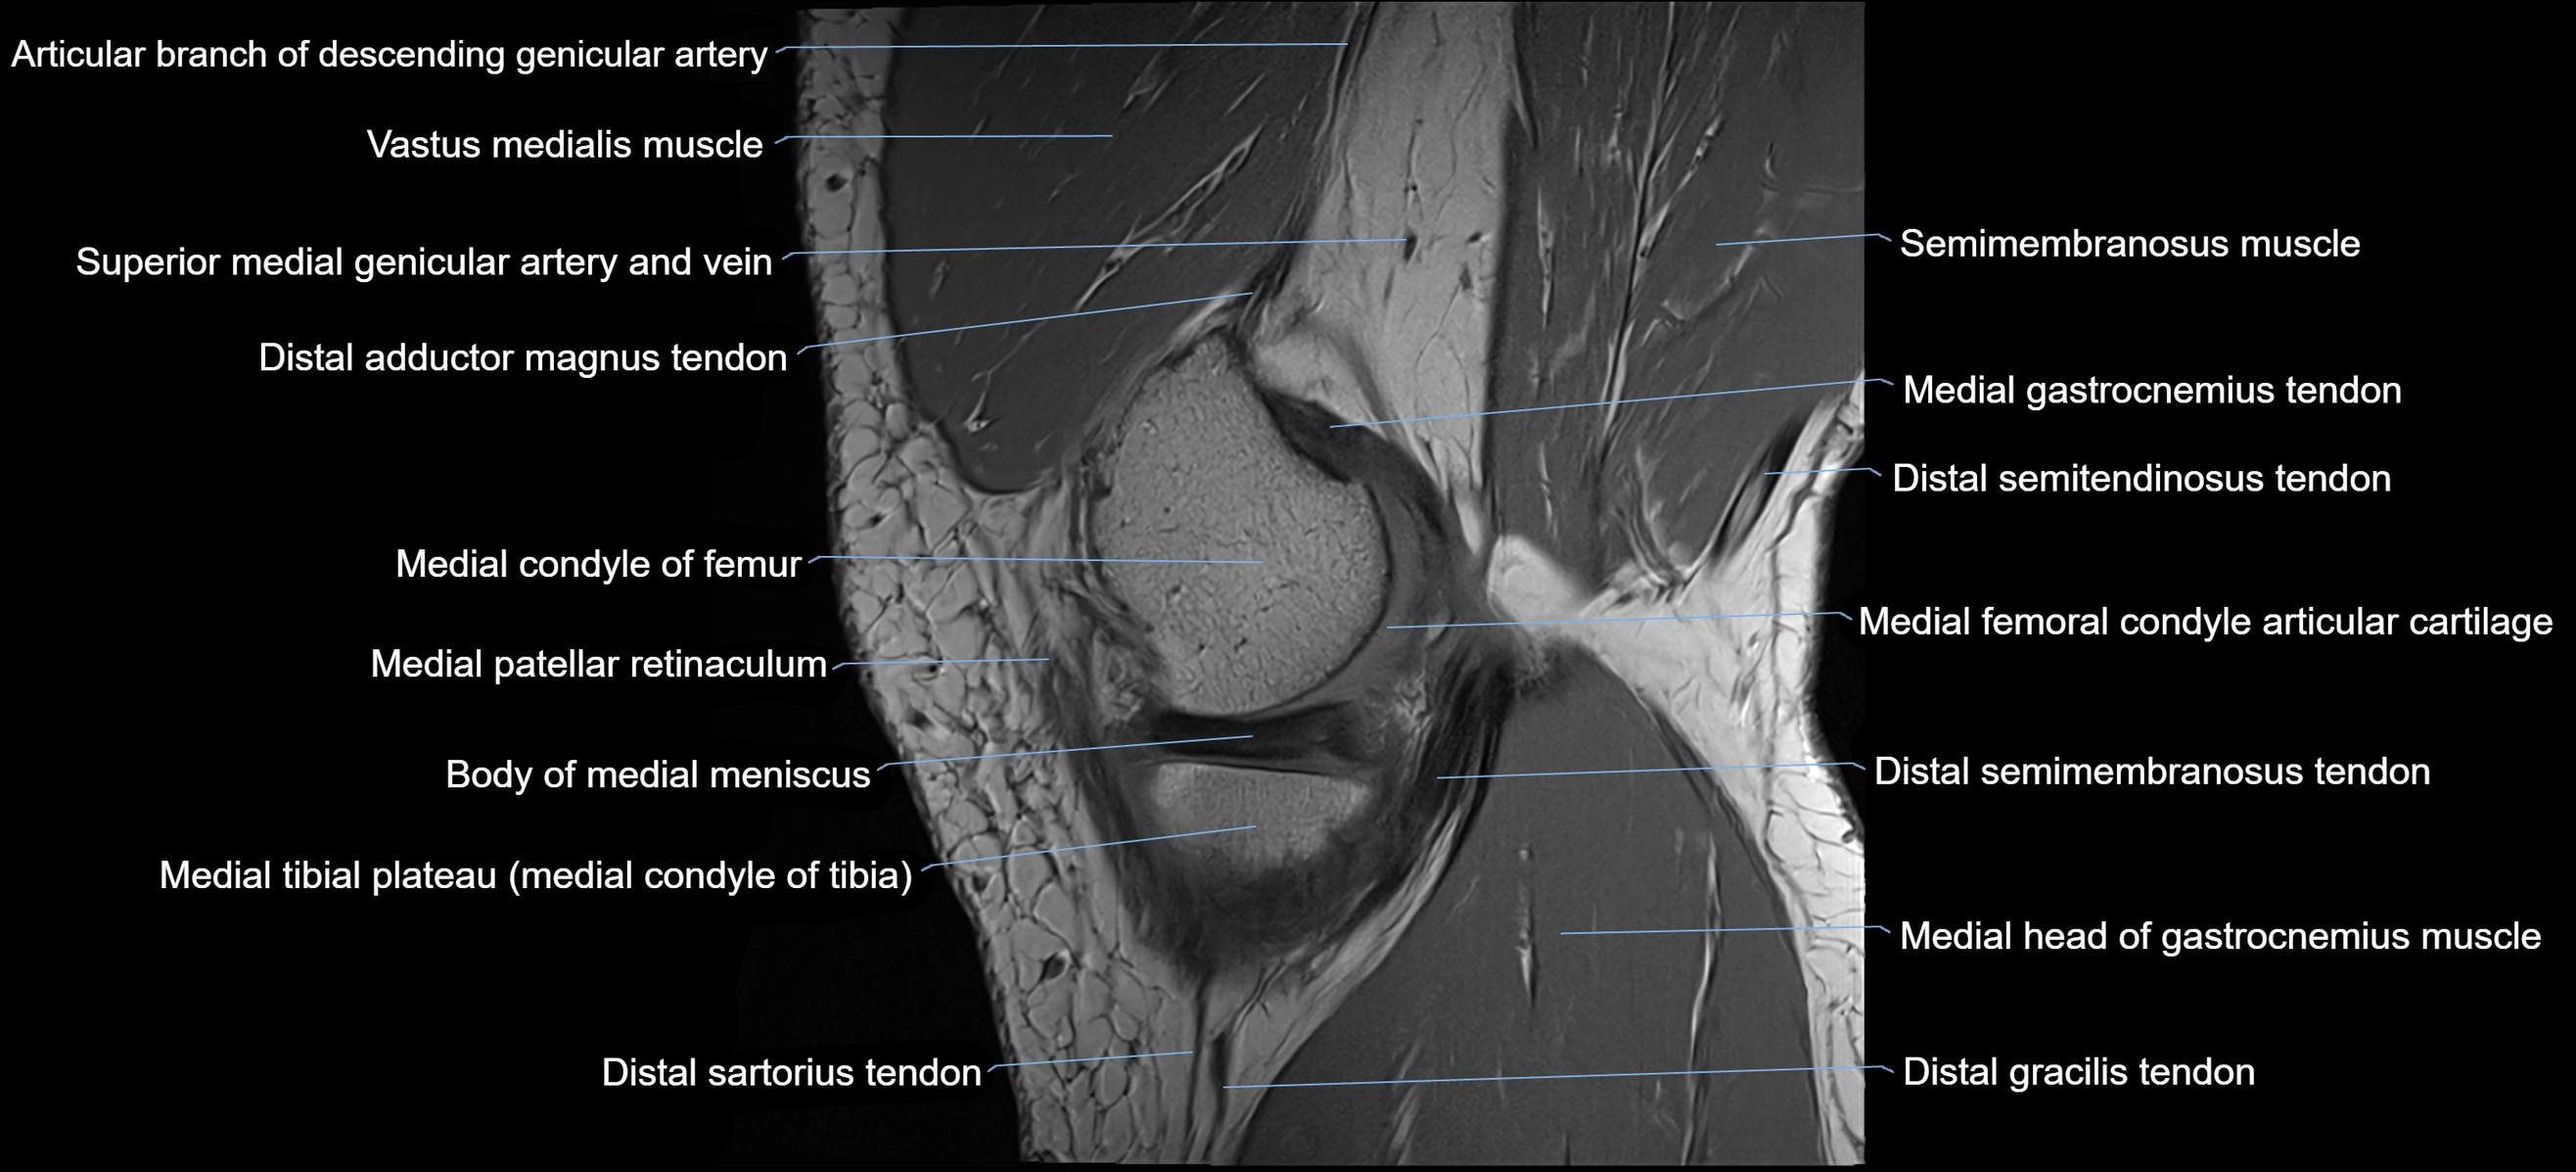

- Body of medial meniscus

- Distal adductor magnus tendon

- Distal semimembranosus tendon

- Distal semitendinosus tendon

- Gracilis tendon (Distal)

- Medial condyle of femur

- Medial condyle of tibia

- Medial gastrocnemius tendon

- Medial head of gastrocnemius muscle

- Medial patellar retinaculum

- Medial tibial plateau